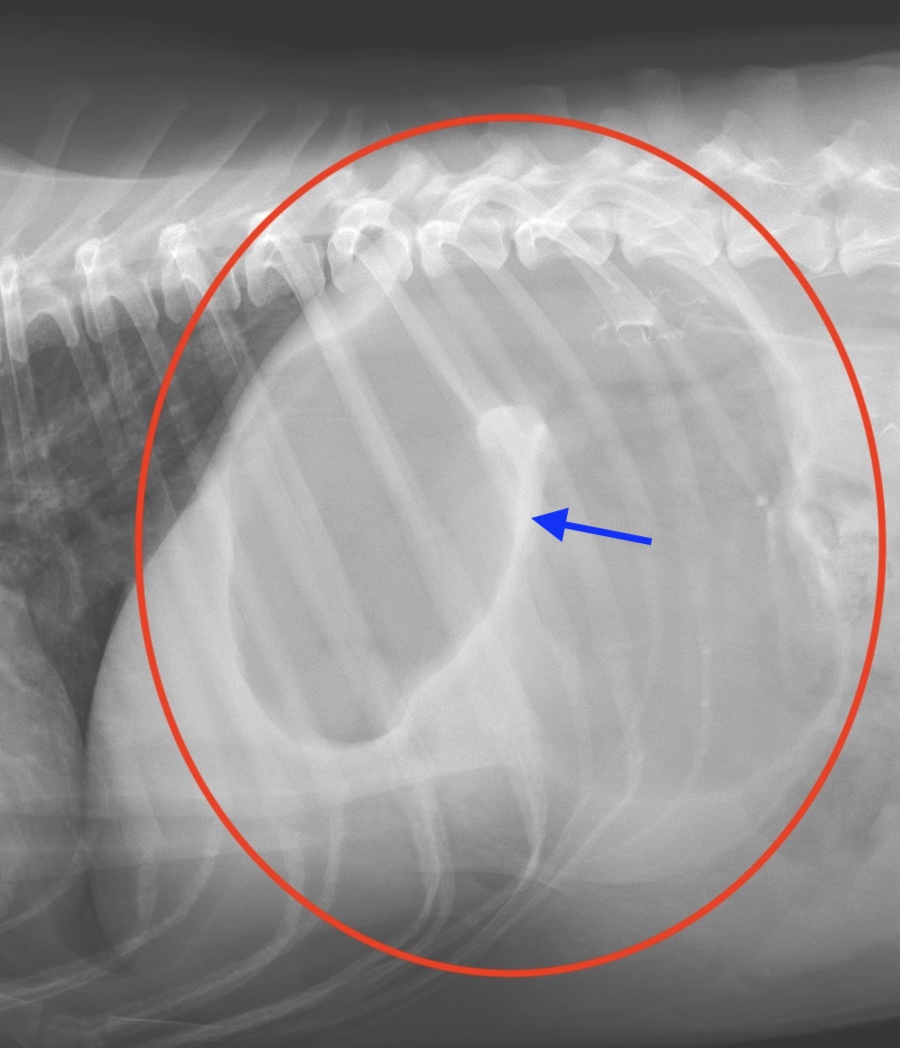

胃拡張胃捻転症候群のレントゲン画像(赤丸)

胃の部分に白いライン(青矢印)がみられるのが特徴です。